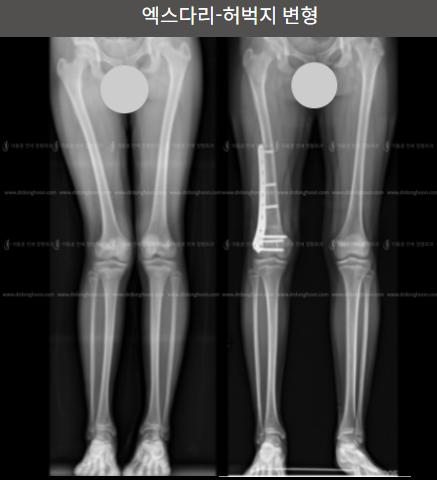

엑스다리-허벅지 변형

허벅지뼈의 변형으로 인한 엑스다리를 교정하였습니다